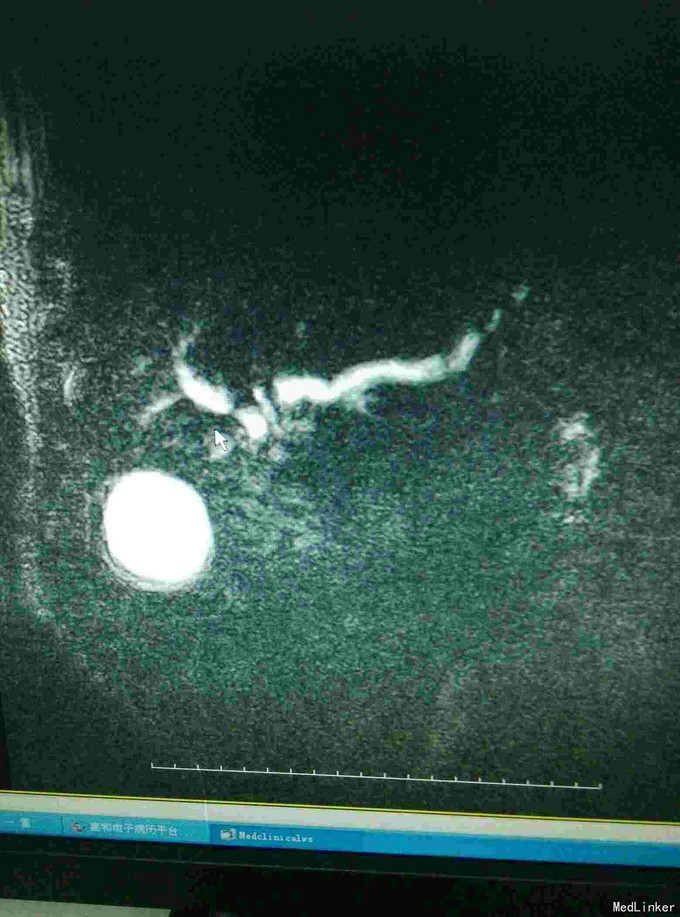

全身皮肤黄染,虹膜黄染,心肺未见异常,腹部稍膨隆,肝区轻度扣击痛,Murphy症阴性。腹部查体腹部B超提示:肝内外胆管扩张,胆囊结石,胆总管下端可见低回声团。MRI如下:

梗阻性黄疸,择日进行了“胆囊切除,胆肠吻合术”,术中见胆囊及上段胆总管明显扩张,下段胆总管塌陷。

此例为下段胆总管梗阻伴胆管多发结石,ERCP切开取石适合单发或少发肝外胆管结石,而胆总管切开取石+T管引流适合单纯胆总管结石,胆肠吻合中胆管空肠吻合常用,此例选择此术式。但此术式毕竟破坏了原有结构,括约肌功能未得以保留,易诱发感染。 术后注意饮食,避免过度油腻食物,注意随访。